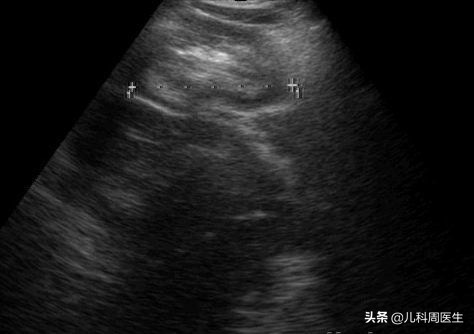

▶腹部B超检查:通过B超在套叠的部位可见类似“同心圆”或“套筒样”超声影像,方便、快捷,无辐射。另外一种就是B超监视下水压灌肠,可以诊断和治疗同时进行。

同心圆样改变